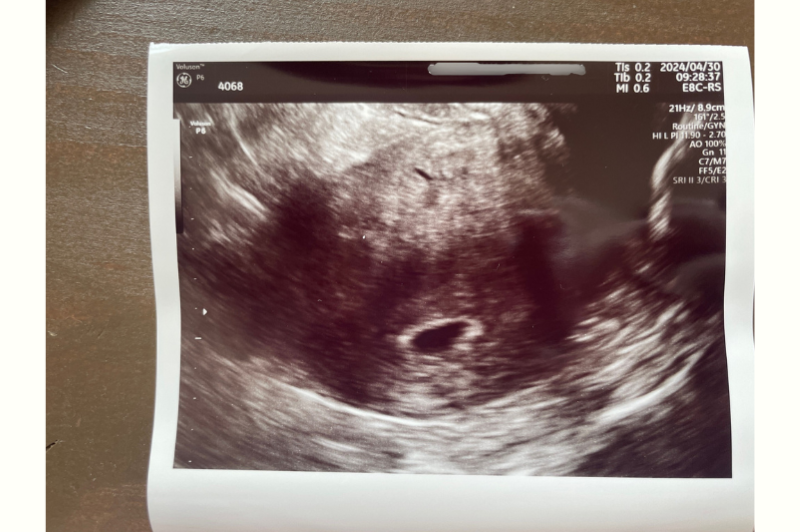

妊娠5週時点の胎嚢。